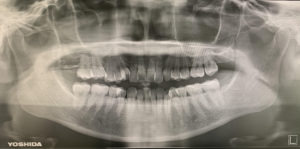

私たちが検査で使う、歯の根っこや骨が白黒で見れるあの写真を撮影するために必須の電磁波です‼

普段見えない歯と歯の間の虫歯を見つけたり、歯の根っこの先の病気を見つけたり、顎の関節を確認できたり、骨の異常を見られたり等✨

その他色んな発見確認ができるので、歯科にとっては必要な診断材料ですね😊